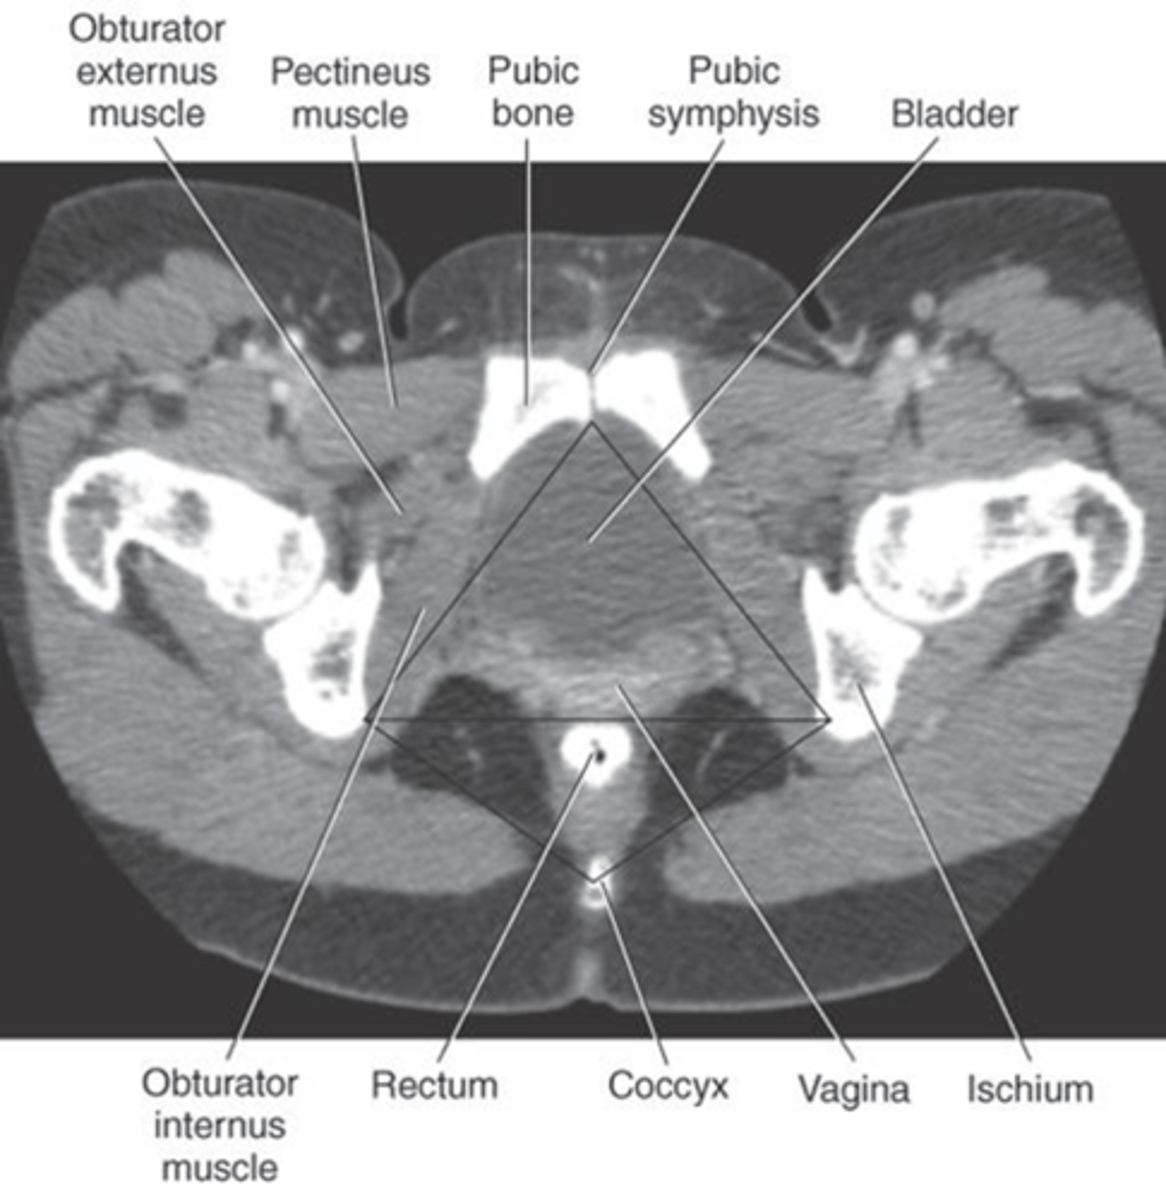

1) Pubic bone

2) Pubic symphysis

3) Bladder

4) Rectum

5) Coccyx

6) Vagina

7) Ischium

Name all numbered structures

1) Coccyx

2) Rectum

3) Vah jay jay

Name all numbered structures